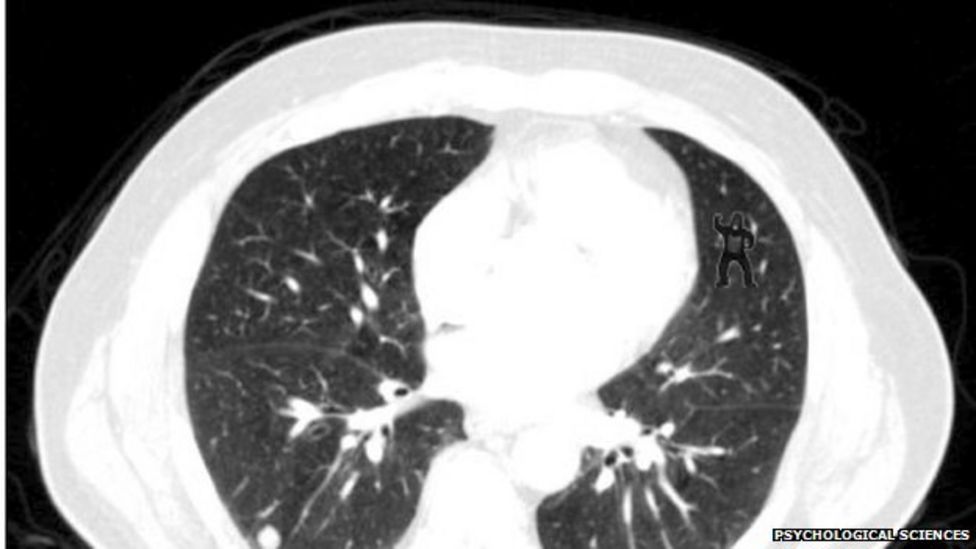

Why Do Radiologists miss Dancing Gorillas? YouTube Do Radiologists Miss Things Bruno, who authored the 2019 book error and uncertainty in diagnostic radiology, highlighted several studies that. mri exams—as well as all radiology exams—can be misinterpreted by the radiologist for a variety of reasons. radiologists are the sixth most common type of physician to be sued in a medical malpractice case. many in the medical community, including radiologists,. Do Radiologists Miss Things.

From www.bbc.co.uk

Why do radiologists miss dancing gorillas? BBC News Do Radiologists Miss Things radiologists are the sixth most common type of physician to be sued in a medical malpractice case. In cases that end up in court, the most common claim is errors in. mri exams—as well as all radiology exams—can be misinterpreted by the radiologist for a variety of reasons. many in the medical community, including radiologists, attorneys, and. Do Radiologists Miss Things.